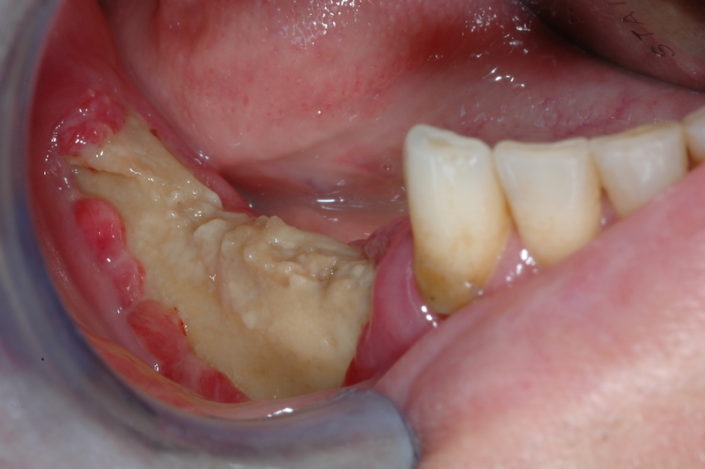

caso di osteonecrosi mandibolare inferiore di destra

Chirurgia

L’approccio chirurgico prevede l’asportazione dell’osso necrotico ed è generalmente consigliato per gli stadi più avanzati e o terminali della MRONJ.

L’intervento chirurgico rappresenta il rischio di recidiva con estensione delle aree di esposizione ossea e aggravamento dei sintomi. Diverse alternative e terapie aggiuntive (laser a basso livello, ossigeno iperbarico, ozono terapia) e diversi agenti biologici (contribuzione piastrinica autologa, concentrati, fattori di crescita e differenziazione ricombinanti, ormone paratiroideo) sono stati proposti in letteratura con risultati positivi.

Programmare un’ intervento chirurgico dovrebbe quindi rappresentare l’ estrema ratio per la risoluzione di questa problematica.

Segno clinico maggiore:

- Esposizione osso necrotico (Cavo orale)